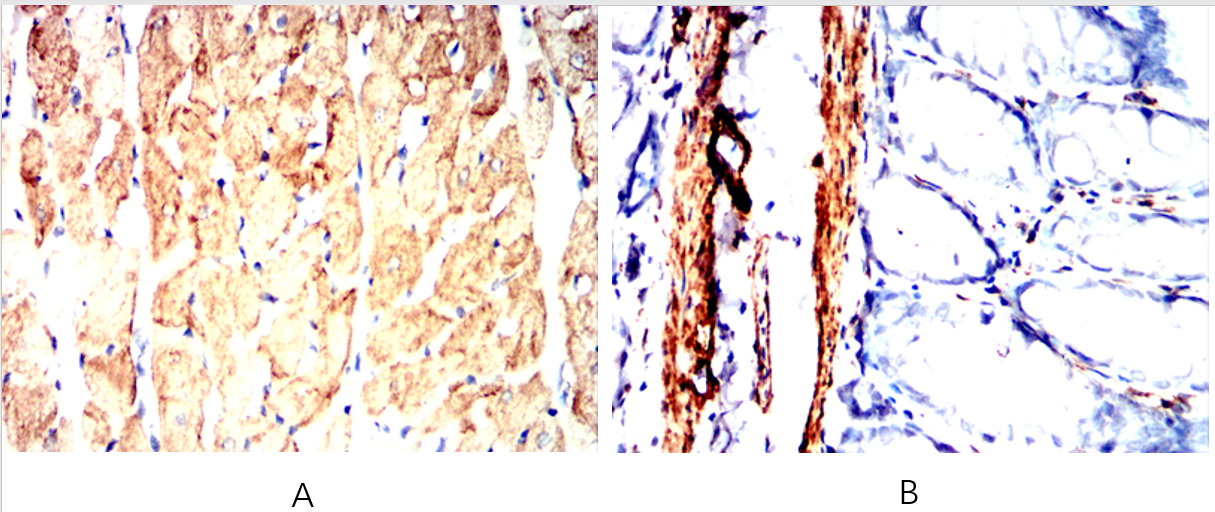

| IHC | IHC:1/100-1/200;IHF:1/50-1/200 | Human,Mouse,Rat |